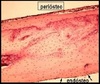

Periósteo

Composição?

Camada fibrosa + osteogênica.

Periósteo

Localização?

Superfície externa da diáfise do osso.